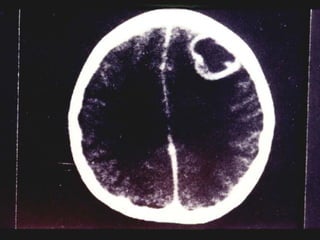

MENINGITIS BACTERIANA Diagnostico: Otros estudios de utilidad: Tomografía axial computarizada. Resonancia magnética.

MENINGITIS BACTERIANA Diagnostico:Otros estudios de utilidad: Tomografía axial computarizada. Resonancia magnética.